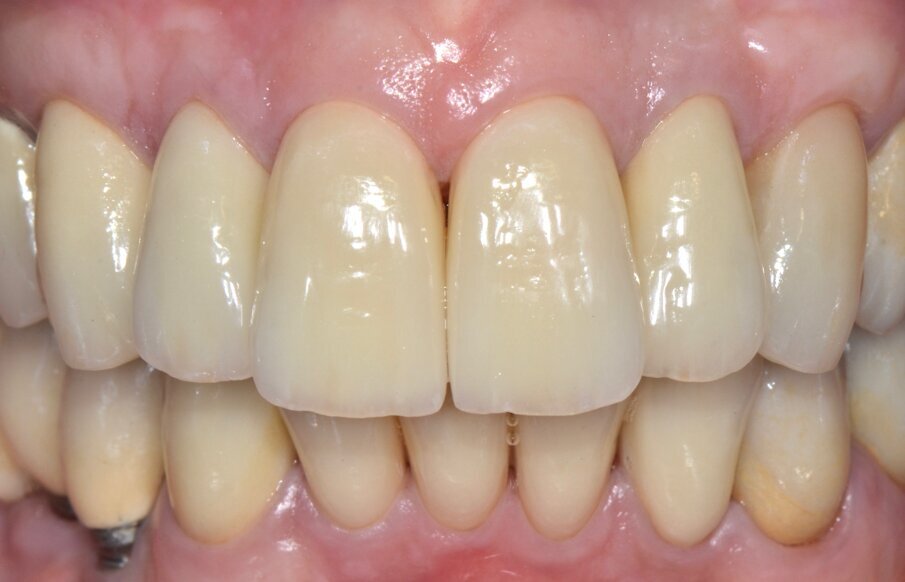

Valutiamo di aver raggiunto una buona simmetria delle parabole gengivali per cui si può procedere con la finalizzazione protesica (Fig. 20). I monconi sono stati preparati con una preparazione verticale per dare priorità alla robustezza dei monconi stessi nella zona cervicale (Figg. 21, 22).

Dal momento che si tratta di un caso estetico senza coinvolgimento parodontale la preparazione è stata molto delicata nei confronti dei tessuti con un posizionamento previsto delle corone definitive leggermente intrasulculare. Una buona conoscenza della fisiopatologia del parodonto unita ad una ottimale gestione degli aspetti protesici dimostra che con ogni tipo di finishing-line si possono ottenere risultati estetici soddisfacenti, ben sapendo peraltro che l’estetica dei manufatti protesici dipende soprattutto dalla bravura e dal senso artistico dei nostri odontotecnici.

Le corone definitive, come precedentemente descritto, vengono costruite con tecnologia CAD/CAM per una sottostruttura in zirconia di cui viene verificato l’adattamento e ricercata la precisione seguendo gli stessi criteri noti per una prova fusione di una struttura metallica (Figg. 23-29). Dopo la prova le strutture vengono inviate in laboratorio per la stratificazione della ceramica.